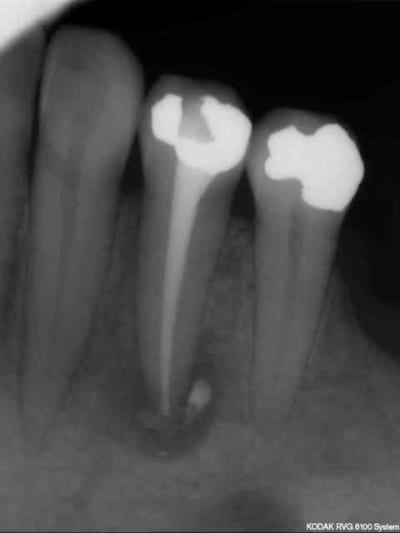

attendriez vous dans ce cas ci:

Patiente consulte avec une cellulite carabiné sur 44; trépanation -antibio, hydoxyde de calcium à plusieurs reprises puis traitement endo définitive.

Après tous ces traitements, je ne pense pas que j'arriverai finalement à la sauver car un nouvel épisode infectieux s'est encore déclaré.

Trois mois séparent les deux radios.

Je vais extraire d'ici quelques jours puis implantation plus tard.

Je ne veux pas faire d'implantation immédiate même avec un curetage soigneux de la lésion, mais je souhaite raccourcir au maximum les délais pour préserver la crête vestibulaire, les papilles, etc...

Quel est le temps le plus court possible avant l'implantation d'après vous?

Je ne suis pas tres sur ,mais il me semble qu'il ya un debut de changement positif a la radio.Est ce qu'il te semble possible de patienter encore?